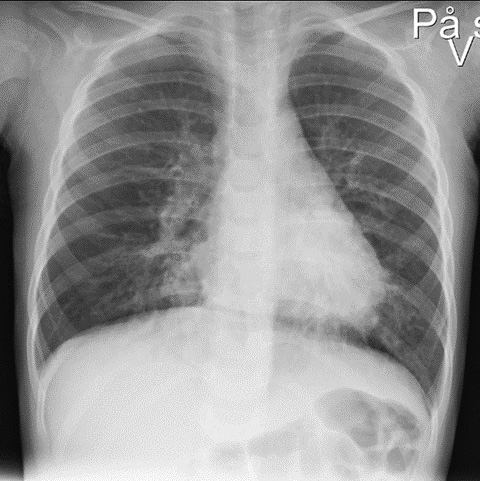

Tilstanden ble tolket som pneumoni, og pasienten ble innlagt på barneavdelingen. Det ble gitt 315 mg penicillin intravenøst og startet oksygenbehandling med nasal høyluftstrømskanyle med hastighet på 15–25 liter per minutt og 40 % oksygentilskudd. Inhalasjoner med 3 ml NaCl og 2,5 mg salbutamol hadde usikker effekt. Røntgen toraks viste perihilære fortetninger (figur 1). Etter fem timer virket barnet mer medtatt, men fulgte fortsatt med på omgivelsene rundt seg. Respirasjonen var hvesende med forlenget ekspirium. Vakthavende barnelege hørte svekkede respirasjonslyder på høyre side.

De fleste barn som vurderes med mistanke om fremmedlegemeaspirasjon, får utført røntgen toraks (> 80 %), og 30–50 % av disse beskrives å ha normale funn (3, 5). Bildet av denne pasienten viste infeksjonsforandringer, men ingen mistanke om fremmedlegeme. Basert på anamnesen med to uker med hoste, kan man i ettertid tenke seg at barnet har hatt en lettgradig viral luftveisinfeksjon i tillegg.